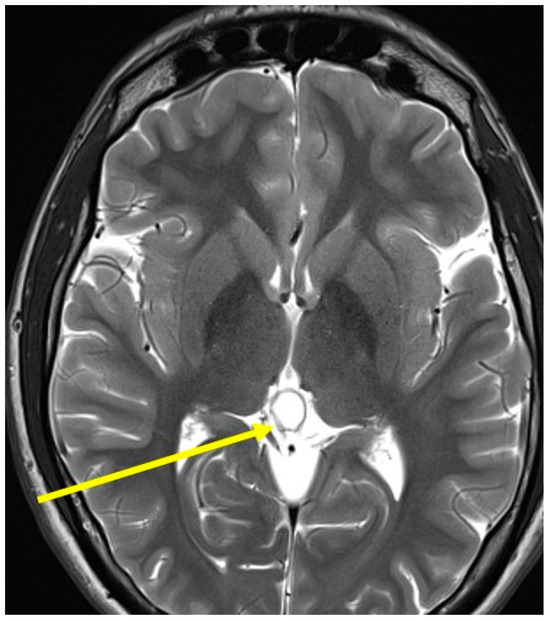

2. Case Presentations